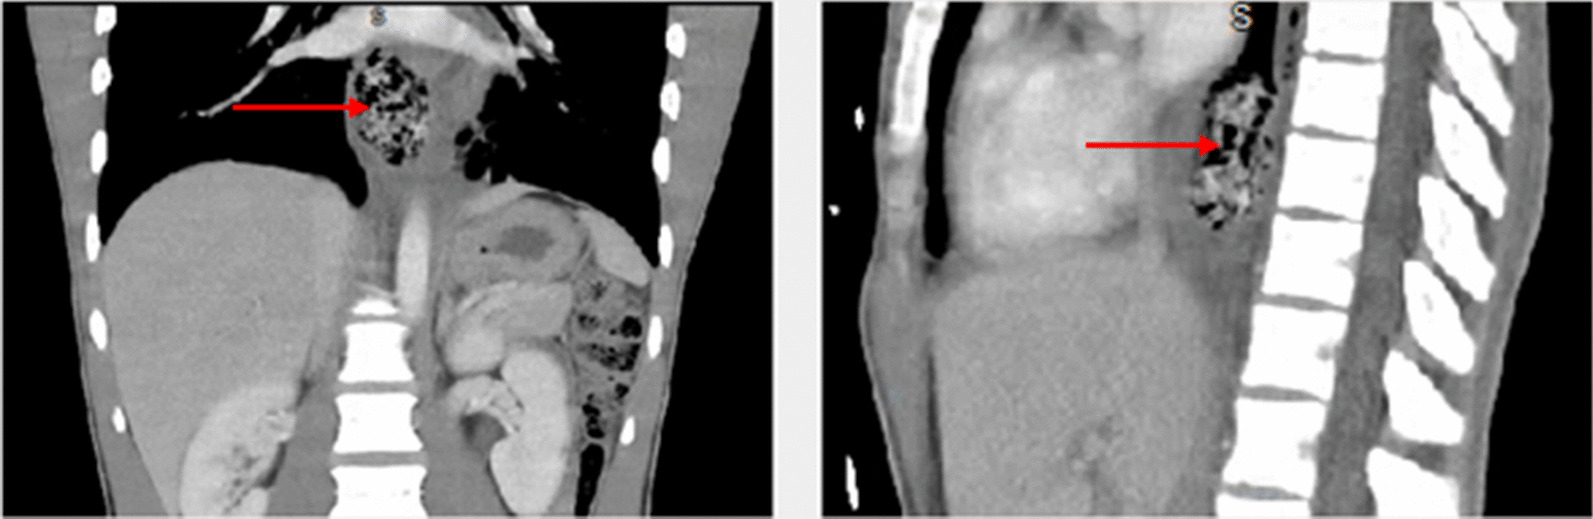

On the basis of the assessment by the on-call physician, he was transferred to a local emergency department (ED) for further evaluation. In the first ED, physical examination indicated a normotensive, mildly tachycardic patient with moderate epigastric pain and otherwise normal physical examination. He admitted that his vomiting has improved but he still continues to have dysphagia. The patient underwent a series of laboratory tests that included complete blood count, serological liver function tests, a complete serum chemistry panel, and a computed tomography (CT) of abdomen and pelvis with intravenous contrast. The initial laboratory findings were significant for a mild leukocytosis, and the CT revealed pericholecystic fluid, distal esophageal edema, and dilation with questionable air in the esophageal wall, and possible hiatal hernia (Fig. 2).